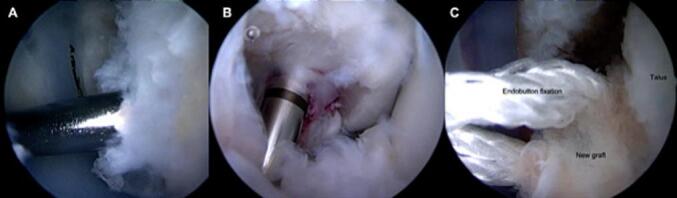

Due to the graft rupture and persistent instability despite 6 months of rehabilitation, in May 2020 the patient underwent revision lateral ligament reconstruction of the ankle with a new arthroscopic anatomical autograft procedure. The contralateral gracilis tendon was used. The procedure was performed by the same surgeon. The surgical technique was similar, with, in particular, the use of the initial tunnels, without difficulty. The rest of the arthroscopic exploration was normal (Fig. 2, Fig. 3, Fig. 4; Video 1, Video 2). The postoperative follow-up protocol was identical to the first procedure.

Fig. 2.

Per operative arthroscopic view.

Fig. 3.

A,B,C Surgical step.